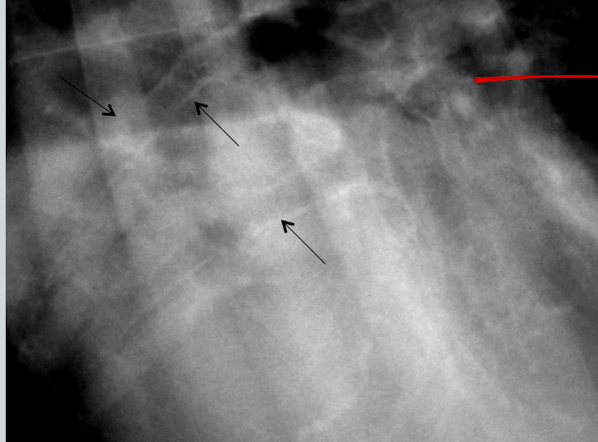

What is the likely condition? What are the arrows pointing to?

Aspiration pneumonia (bc right middle)

red: air bronchogram

blue: border effacement

yellow: lobar sign